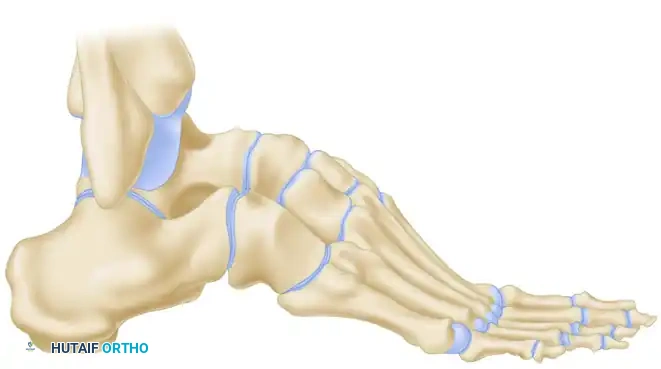

SURGICAL ANATOMY OF THE PERONEAL TENDONS

Understanding the spatial relationship of the peroneal tendons is paramount for safe harvest and routing.

- Proximal to the Fibula: The peroneus longus and brevis share a common synovial sheath within the retromalleolar groove.

- At the Fibula: Immediately posterior to the lateral malleolus, the peroneus longus lies anterior or superficial to the brevis tendon.

- Distal to the Fibula: This relationship changes as the tendons rotate; the brevis tendon becomes superficial and inserts onto the base of the fifth metatarsal.

Surgical Warning: The brevis tendon can be easily identified proximally because its muscle fibers extend much further distally on the tendon compared to the peroneus longus, which has no attached muscle at this level.